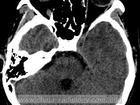

(二)電子計算機斷層掃描(簡稱CT) 可顯示擴大的垂體窩,窩內垂體萎縮,充滿低密度的腦脊液。